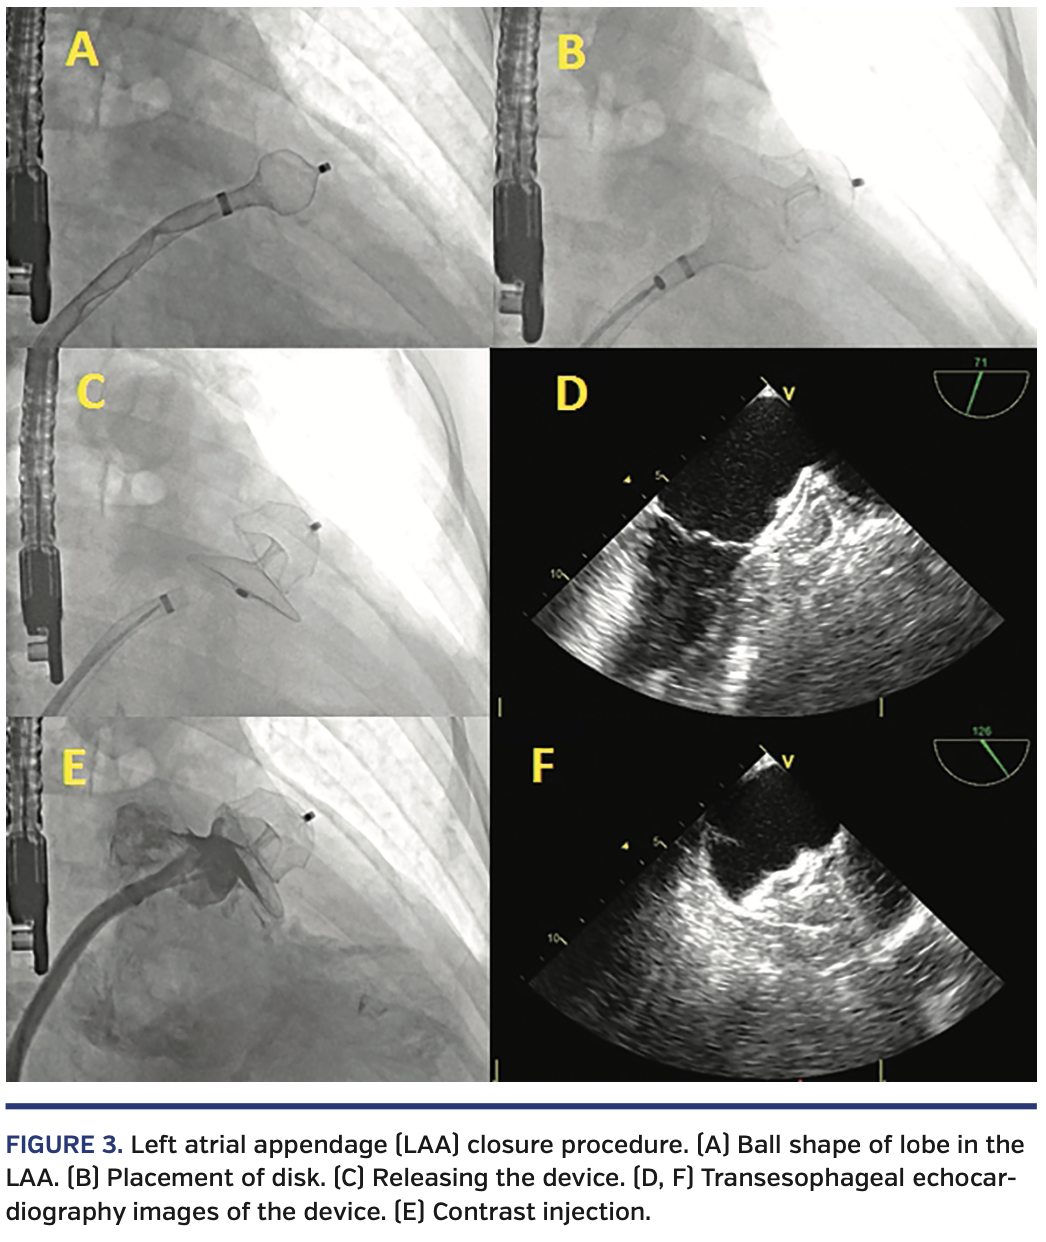

The percutaneous LAA occlusion procedure was performed under general anesthesia in all patients, and patients were intubated for optimal TEE guidance. Transseptal puncture was performed with fluoroscopy and three-dimensional (3D) TEE guidance. Transseptal puncture was performed at the inferoposterior site of the interatrial septum if there were no anatomic variations that prevented optimum orientation. After successful transseptal puncture, the delivery catheter was placed in the left atrium. An Amplatzer Amulet LAA occlusion device (Abbott Vascular) was advanced to some extent out of the delivery sheath in order to form a ball shape with the lobe of the device. The delivery sheath with the ball-shaped device on the tip was then placed in the LAA with counter-clockwise rotation, avoiding any unnecessary manipulation. The LAA was not engaged with a pigtail catheter and contrast injection was not performed to avoid embolization of the thrombus. All measurements and device size selections were based on TEE. After confirming the optimum settlement in the LAA with TEE, the lobe of the device was opened with further advancement. To prevent catheter-induced thrombus embolization, inappropriate catheter manipulation in the LAA was avoided. After proper placement of the lobe in the LAA, the disc was opened at the ostium of the LAA with withdrawal of the delivery sheath (Figure 3). The relationship between the occlusion device and the circumflex artery/mitral valve were checked with 3D-TEE and radiopaque contrast was injected within the delivery sheath to evaluate peridevice leak. Before releasing the device, it was pulled back with enough force to check the stability. The occlusion device was then released, and the relationships between the device and LAA, circumflex artery, and mitral valve were evaluated by 3D-TEE. Periprocedural anticoagulation was maintained by intravenous heparin infusion with activated clotting time monitoring.

In our series, we refined the Amplatzer Amulet implantation technique to avoid embolization of the thrombus in the LAA during the procedure. First, we took maximum precautions to avoid any engagement of wires or catheters in the LAA. Contrast injection with pigtail catheter was not performed and measurements were based on TEE. The device delivery catheter with the ball-shaped device on its tip was advanced into the LAA with a single maneuver in a “one shot” manner. After demonstrating the appropriate position in the LAA with TEE, the device lobe was opened with further advancement, without any pullback in the delivery catheter. Finally, all 80 procedures, including the 12 with LAA thrombus, were performed by the same operators and cardiovascular imaging specialist in this single-center series. We believe that this is a major factor for the excellent procedural outcomes reported in this study.